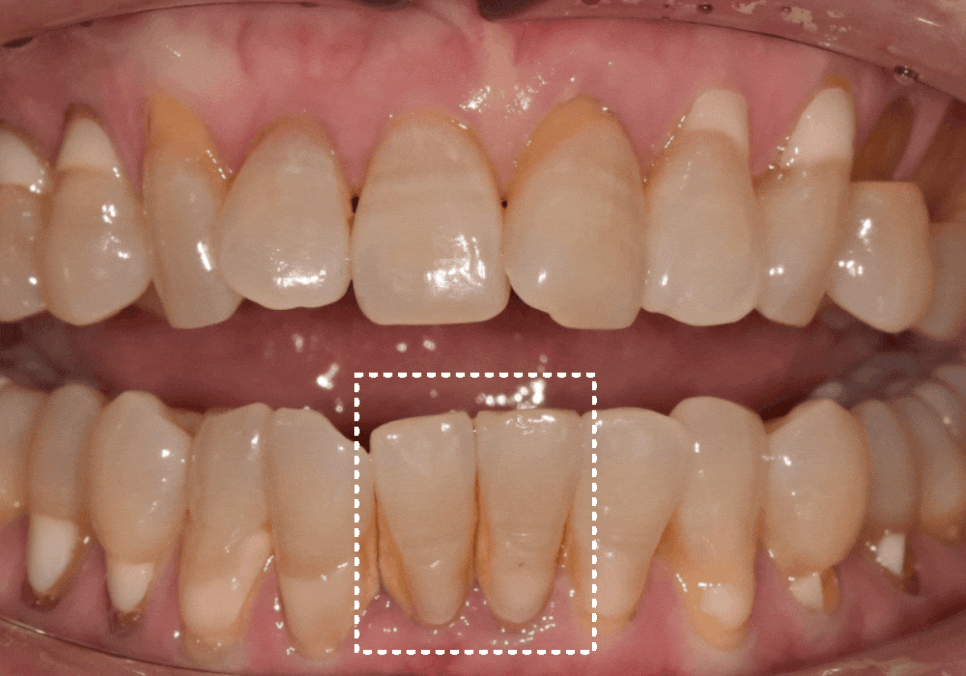

최종 완성된 모습입니다.

뿌리는 1개지만,

보철물은 2개가 들어갔습니다.

전혀 어색하지 않고

주변 치아와 자연스럽게 어우러지죠?

옆 치아의 길이와도 대칭을 이루어

심미적으로도 아주 만족스럽게 마무리되었습니다.